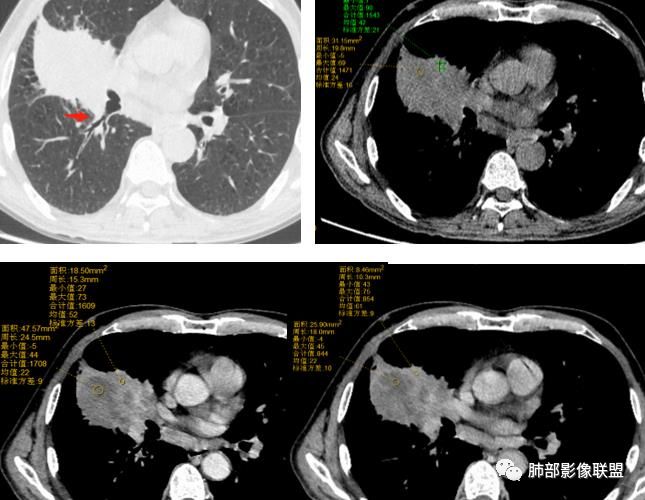

患者中老年男性,体检发现右肺占位。血常规轻度贫血,AFP、CEA正常,肝肾功能、血糖、血脂、心肌酶、电解质正常。胸部CT:右肺中叶巨大肿块灶,垮叶生长,可见分叶、毛刺、血管集束、支气管截断征象,远端周围可见小叶间隔增厚,增强轻度强化,内可见低密度坏死区,综合淋巴结肿大,且可见淋巴结内似低密度灶。综合考虑恶性,鳞癌并癌性淋巴管炎可能大。鉴别结核、腺癌。

胸CT:右肺中叶团块样实性占位,边缘膨隆,中叶外侧段阻塞,病灶可见深分叶、棘突,胸膜牵拉;增强不均匀强化,可见边缘模糊血管影,病灶内大片状低密度区,纵隔多发肿大淋巴结。

诊断考虑:恶性病变,鳞?大细胞?鉴别:TB

右肺中叶肿块影,向上向下侵犯叶间裂,边缘膨隆,分叶,毛刺。肿块内部密度不均,大片坏死。血管走形尚可。中叶支气管狭窄截断。增强不均匀强化。纵隔淋巴结肿大,部分融合。

考虑恶性,腺癌>鳞癌。鉴别炎肌母。

晨读:右中为主肿块,跨叶,右中叶外侧支闭塞,病灶有坏死,远侧少许小叶间隔增厚,考虑恶性,腺癌大于鳞癌。结合有无吸烟史

1.具有肉瘤的特性:肿瘤体积一般较大,直径约大于5cm,边缘清楚、光整,由于肿瘤生长迅速,可见大片坏死,坏死边界清楚;常见支气管推移。

2.具有癌些特性:如分叶、短毛刺、空洞,但是钙化及胸膜凹陷征少见,病灶往往是直接侵犯胸膜,可以远处转移,肺门及纵隔淋巴结可明显肿大;

3.强化方式:增强后病灶以环状强化为主,病灶周边多以癌组织为主,血供丰富,病灶中心区则以肉瘤成分为主,血供较差,易出现粘液样变性、坏死、出血,坏死边界清楚,所以增强CT对PSC与普通型肺癌有一定的鉴别价值。

3.坏死区边界较清楚(皮囊样),环形强化明显,病灶内血管穿行等,都不符合我们常见的鳞癌。